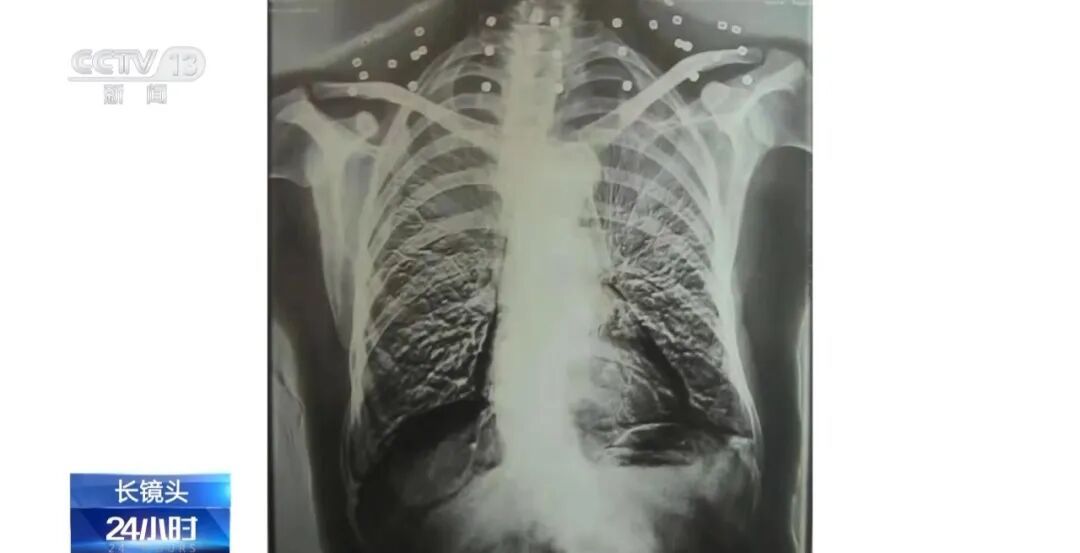

2025-10-19“爷爷,把衣领摘下来,做个CT吧。” “看看是

这张照片是82岁吴以贤的CT扫描。拍完照片后,医生说:“医生,请把项链摘下来再做CT。”...